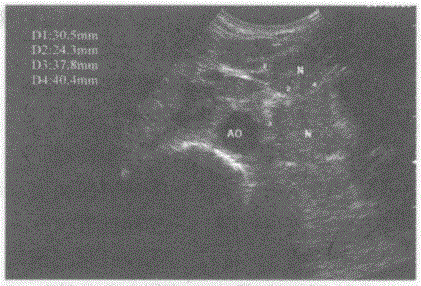

临床资料:男,50岁,肺癌术后肝转移。超声综合描述:腹主动脉前方可见多个大小不等低回声,最大4.0cm×2.3cm,边界尚清晰,形态不规则,部分相互融...

问题 临床资料:男,50岁,肺癌术后肝转移。 超声综合描述:腹主动脉前方可见多个大小不等低回声,最大4.0cm×2.3cm,边界尚清晰,形态不规则,部分相互融合。 超声提示:

选项 A.腹腔多发肿大淋巴结(淋巴结转移癌) B.腹膜后畸胎瘤 C.胃癌 D.平滑肌肉瘤

答案 A